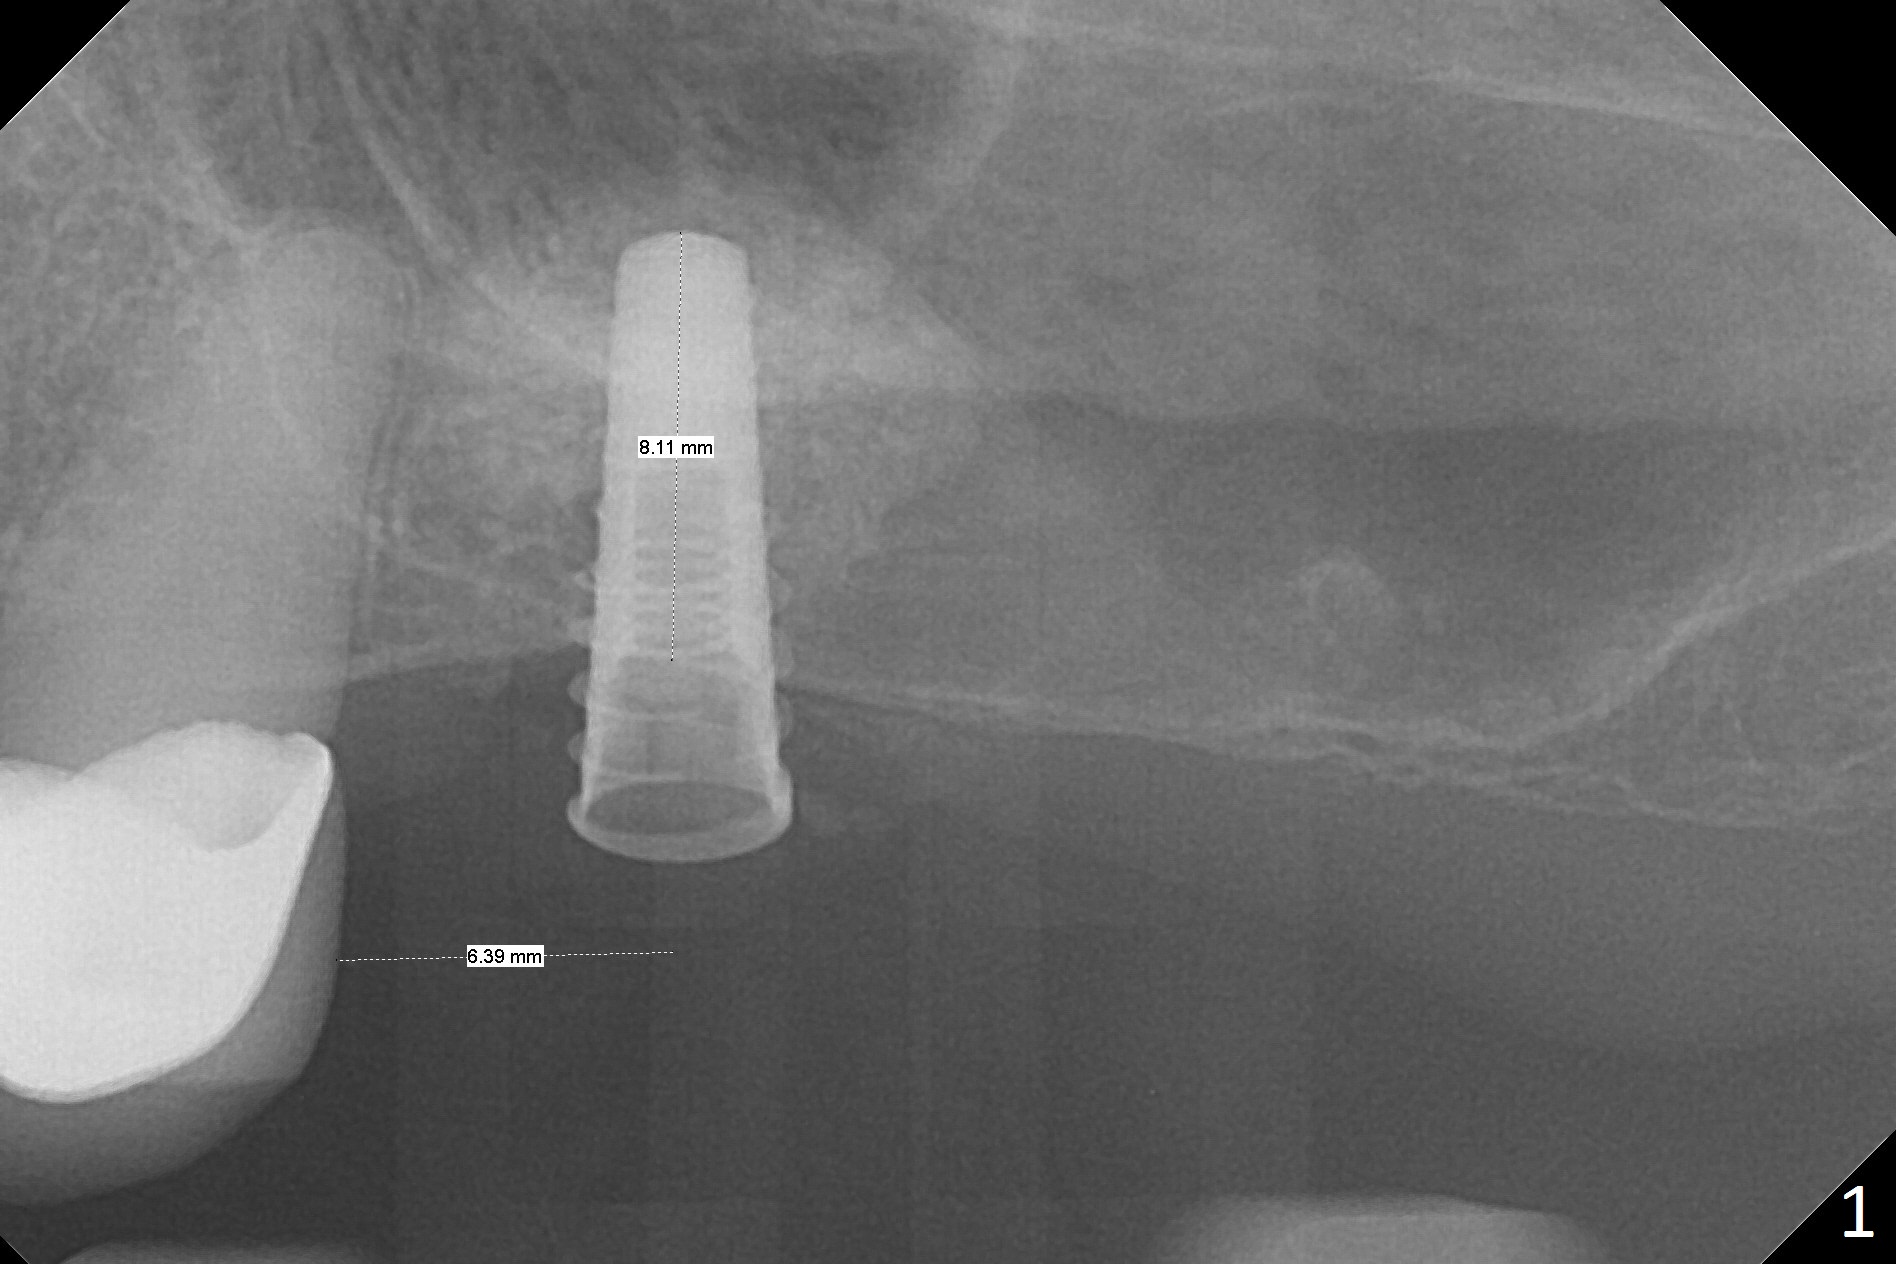

Blood drawing for PRF fails. After NO inhalation and local anesthesia, an incision is made at the narrow ridge of #14. Magic Sinus Lifter is used to elevate the sinus floor for ~ 5 mm, followed by insertion of allograft/Osteogen and 4.0x11 mm dummy implant partially (Fig.1). With approximately 10% more of graft being placed, a 4.5x9 mm IBS implant is placed with insertion torque of 15 Ncm (Fig.2). The shape of the sinus suggests that the primary stability is derived from the contact between the implant and the sinus floor (Fgi.3, preop CBCT coronal section). Approximately .5 mm implant threads are exposed buccodistopalatally, which are covered by allograft and collagen membrane before suturing. There is one episode of nasal discharge postop. The wound dehisces without sign of infection (Fig.4 (1 month 1 week postop)).